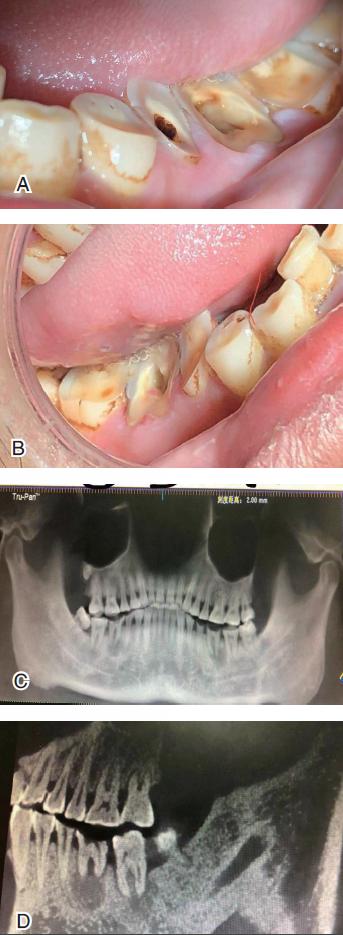

当咀嚼这些槟榔一段时间后,槟榔果实就变成槟榔纤维。这种纤维对口腔黏膜有严重的刺激性。咀嚼时间较长后,口腔的不同组织和器官就会出现不同的病变,如牙齿和牙齿周围组织的病变(图3)、黏膜和颌骨的病变以及颞下颌关节的病变。

长时间咀嚼槟榔会造成上下颌牙齿的磨耗,尤以上下颌前磨牙和磨牙的磨耗最为明显。牙齿的磨耗临床上表现为牙冠颊侧的磨耗较舌腭侧为重。如有牙冠髓腔暴露的情况,可导致急性牙髓炎,长久后可导致慢性牙髓炎的症状和临床表现。如果此时不治疗,就可能进一步发展成为残根。这时,如果不将残根拔除,就会导致残根根尖周围炎甚至导致颌骨囊肿或颌骨骨髓炎(见下文图4)。

近期,有一34岁的槟榔咀嚼者,发现自己的张口度变小,上下颌的磨牙严重磨耗,吃冷热食物及喝凉水时疼痛明显,来湘雅医院口腔医学中心就诊。接诊医师经检查后发现,上下颌磨牙牙严重磨耗,尤以下颌磨牙最为突出,有牙神经外露;患者的张口度为25 mm,双颊及软腭黏膜苍白,有纤维条束存在。双侧面部为方形脸。CBCT检查发现双侧磨牙呈斜形磨耗,疑似残根,根尖有圆形暗影(图4)。最后诊断为:1.中度口腔黏膜下纤维性变;2.上下颌磨牙严重磨耗伴牙髓炎;3.下颌磨牙慢性牙根尖周围炎;4.下颌磨牙残根;5. 继发性张口受限。将患者分别转入相关科室治疗。

图4 34 岁的槟榔咀嚼者的牙齿严重磨耗、根尖病变、下颌角及颞颌关节的位置情况